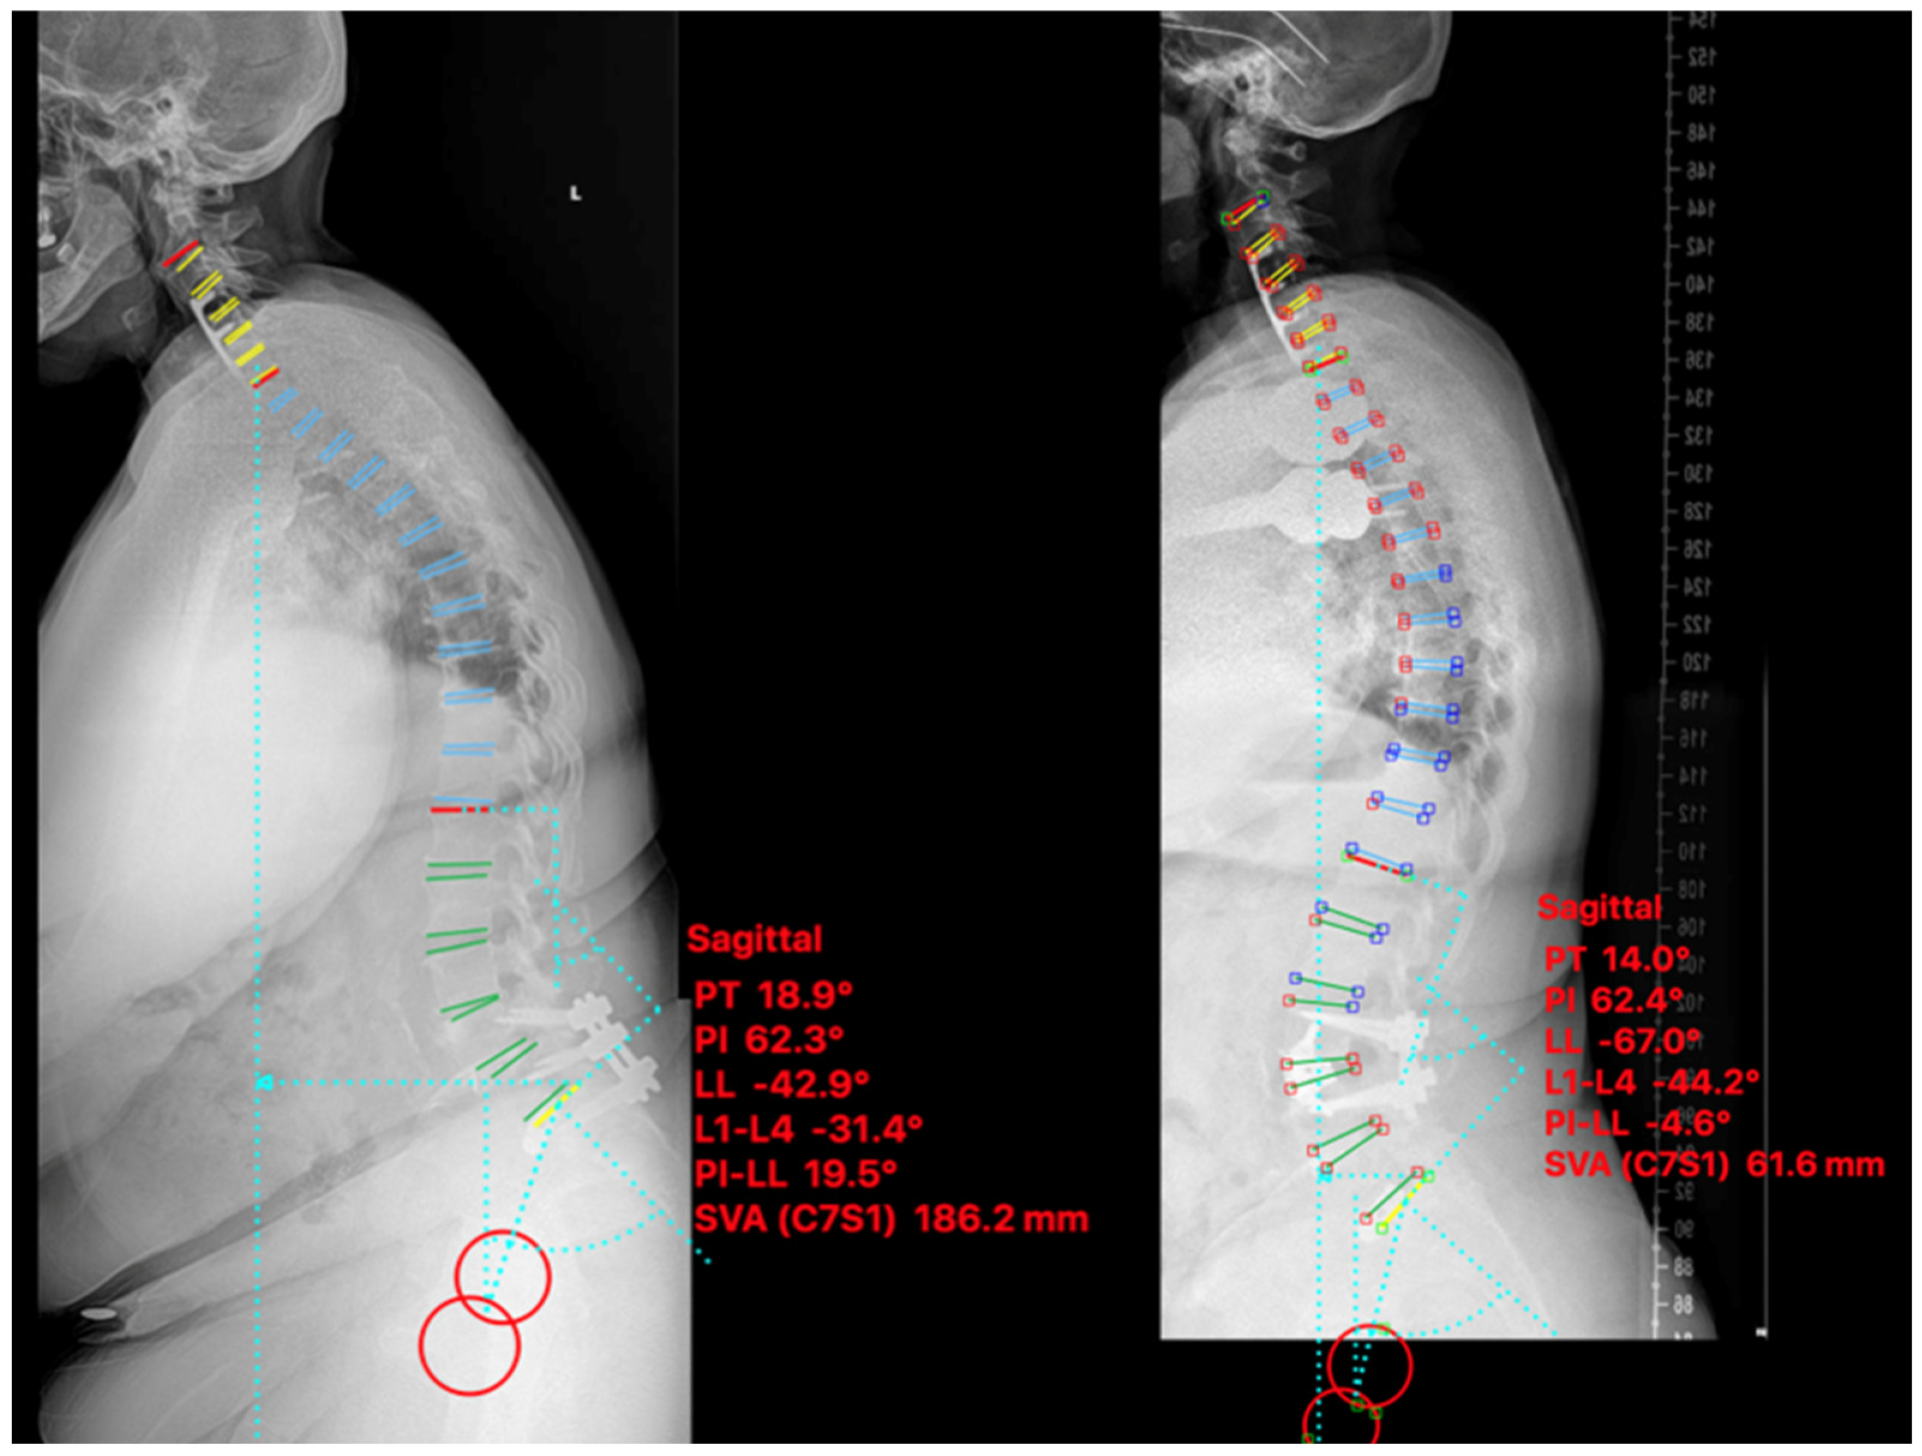

| Pre. | −32.6 | 16.0 | 180.5 | 31.9 | 26.4 | 22.2 |

| Post. | −56.0 | 12.8 | 61.3 | 18.0 | 5.1 | 16.5 |